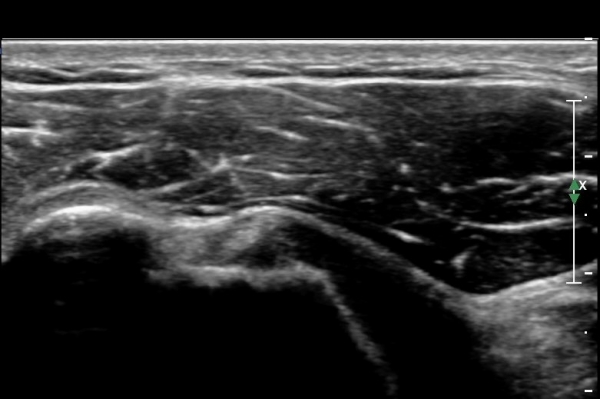

¿À±¸µ¹±â°ßºÀÀδë Á¾´Ü¸é°Ë»ç¿¡¼­ ÀÎ´ë ½ÉÃþ¿¡ ¼ö¾×Àú·ù°¡ °üÂûµÊ(»çÁø 1, 2)

ÀÌ´Â Ãæµ¹ÁõÈıºÀ» ¾Ï½ÃÇÏ´Â ¼Ò°ßÀÓ.